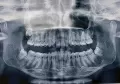

У меня нижняя челюсть на пару миллиметров больше выпирает, чем верхняя, и при смыкании челюстей, нижняя челюсть сдвигается немного вправо.

Без расчета ТРГ снимка в боковой проекции, ответить на сто процентов, необходима ли Вам операция, не представляется возможным.

Возможно закамуфлировать Вашу ситуацию, т.е. нижние зубы немного наклонить кзади, а верхние вперед, но, возможно, Ваш подбородок будет выступать вперед.